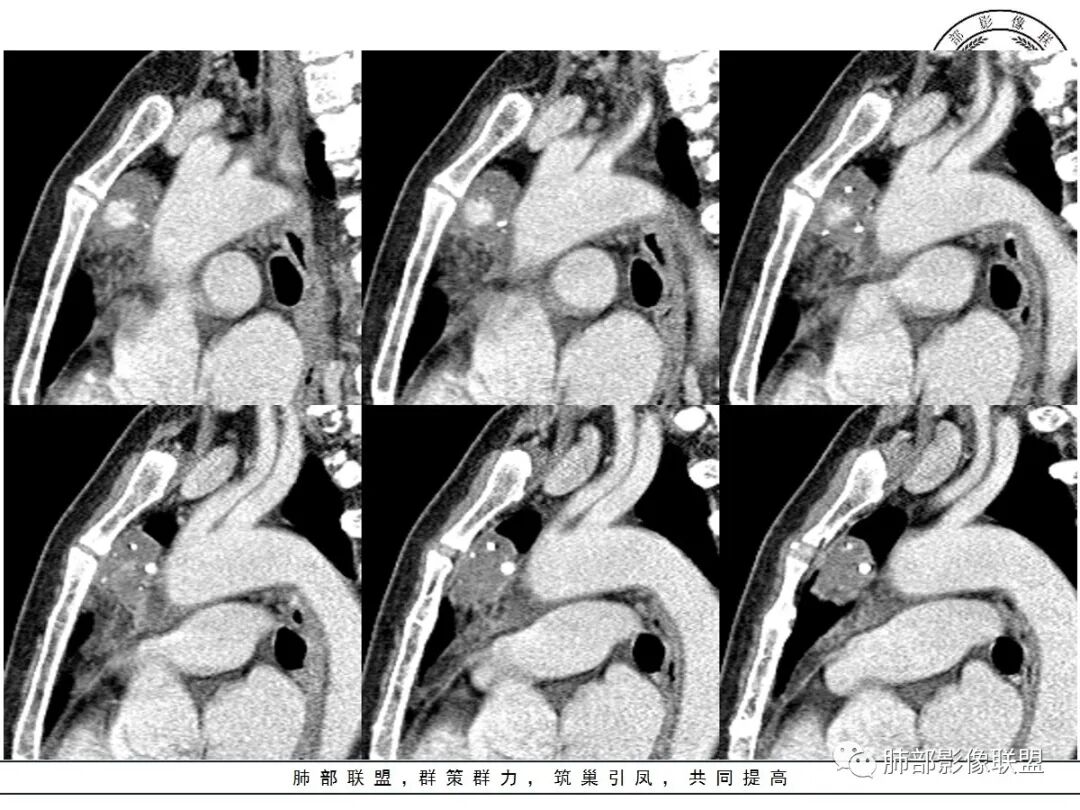

红星:女性病人48岁,前上纵隔,类圆形的实性病变,平扫密度比较均匀,周围卷见点状的钙化灶,增强扫描明显的强化, 多时相扫描中心可见跟大血管强化幅度一致的结节灶。常规胸腺瘤?鉴别血管瘤?

周太狼:中年女性,前纵隔肿块,边界清,内不规则钙化灶,增强中央明显强化,与邻近血管强化程度相似。纵隔内无明显增大淋巴结。考虑良性或低度恶性病变。疾病谱:CD、副节、血管瘤、胸腺瘤/癌。个人倾向于CD或血管瘤可能大一些。

三个石头:前纵隔占位,残余胸腺组织可见,边缘钙化,增强中央出现与血管同步强化结节,病灶延迟强化。脉管瘤?胸腺瘤?血管瘤?异位甲状腺?

中央结节状强化, 类似于血管强化

前纵隔海绵状血管瘤的影像学特征包括:①发生于前纵隔的圆形、类圆形、不规则肿块影,边界清晰,与邻近结构分界清晰;②CT上呈稍低密度影,内见小结节状、小片状、针尖状的钙化灶,钙化灶、静脉石影是海绵状血管瘤的特征性表现。③增强后大多数肿块可显示肿块的范围及供血情况,动脉期病灶边缘呈点片状强化,静脉期及延迟期逐步向内填充,呈渐进性强化等典型特征,部分不强化或轻度强化,部分增强 后片状强化,强化程度与邻近血管相仿;血管瘤强化方式与肿块内组织成分、血窦内血栓、血流等因素有关;Moran等研究表明,肿块强化不均匀或呈轻度强化的原因可能与扩张的血窦腔内组织平滑肌增殖及炎性纤维化有关;肿块血管样强化可提示海绵状血管瘤。前纵隔海绵状血管瘤需与畸胎瘤、胸腺瘤、胸内甲腺肿、神经内分泌肿瘤等进行鉴 别 断:①畸胎瘤多呈混杂密度影,内有脂肪、毛发、钙化灶及水样密度;②胸腺瘤呈结节状、团块状影,密度较均匀,增强后强化较均匀,与周围组织分界清晰;③胸内甲状腺肿位于前上纵隔,平扫密度常较高,可见其上端与颈部甲状腺相连;④神经内分泌肿瘤多伴坏死囊变,点片状钙化,形态常呈分叶状或 不规则形,增强后肿瘤实性部分强化显著。

综上所述,海绵状血管瘤发生在纵隔非常罕见,且缺乏典型的临床症状及特异性影像, 应从肿块的位 置、大小、形态、与周围组织的 关 系 以及CT平扫、增强特点进行分析,如前纵隔肿块内有钙化灶、静脉石、增强后点片状血管样强化及渐进性强化等特点,应考虑纵隔海绵状血管瘤的可能;薄层CT及其多平面重组有利于发现细小钙化灶,而动态增强CT扫描能更好显示肿块内血管强化,有助于术前诊断与鉴别诊断。